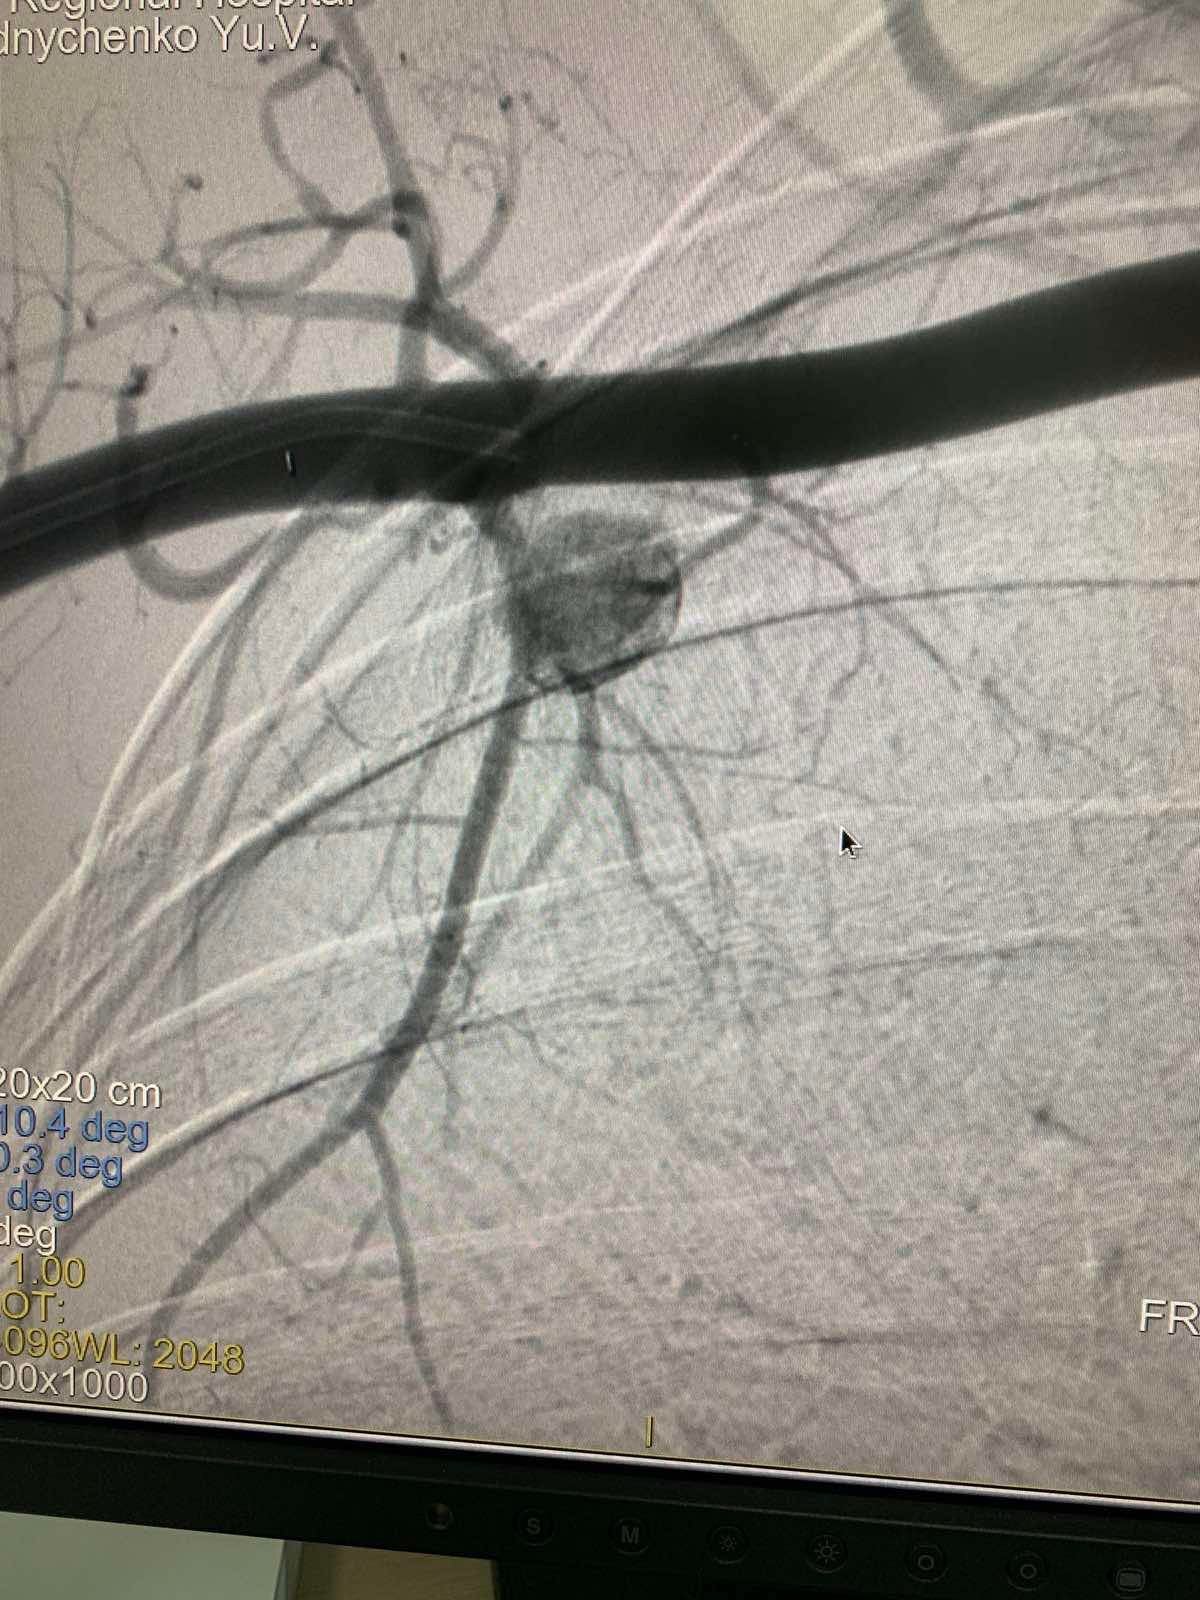

Мигом собралась хирургическая бригада и сделали ангиографию. Оказалось, что был крошечный, практически незаметный рентгену, фрагмент оболочки от извлеченной ранее пули. Этот кусок металла повредил одну из ветвей подключичной артерии.

Медики говорят, что из-за разрыва стенки образовалась ложная аневризма. Врачи еще называют "бомбой замедленного действия". Все потому, что аневризма может в любой момент вызвать несовместимое с жизнью артериальное кровотечение.

Хирурги провели чрезвычайно сложное вмешательство: исключили травматическую аневризму микроспиралями и "заклеили" поврежденные стенки артерии.